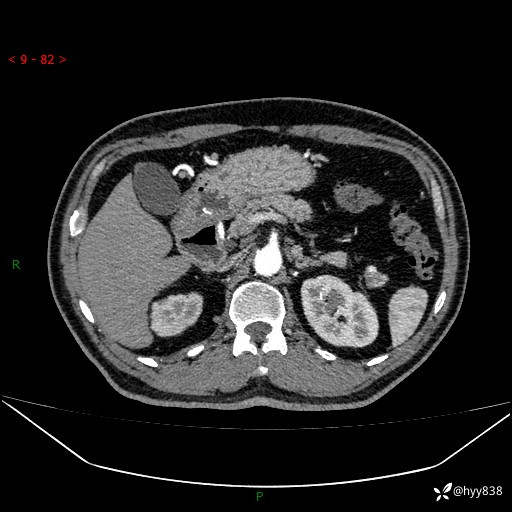

胰腺CT平扫